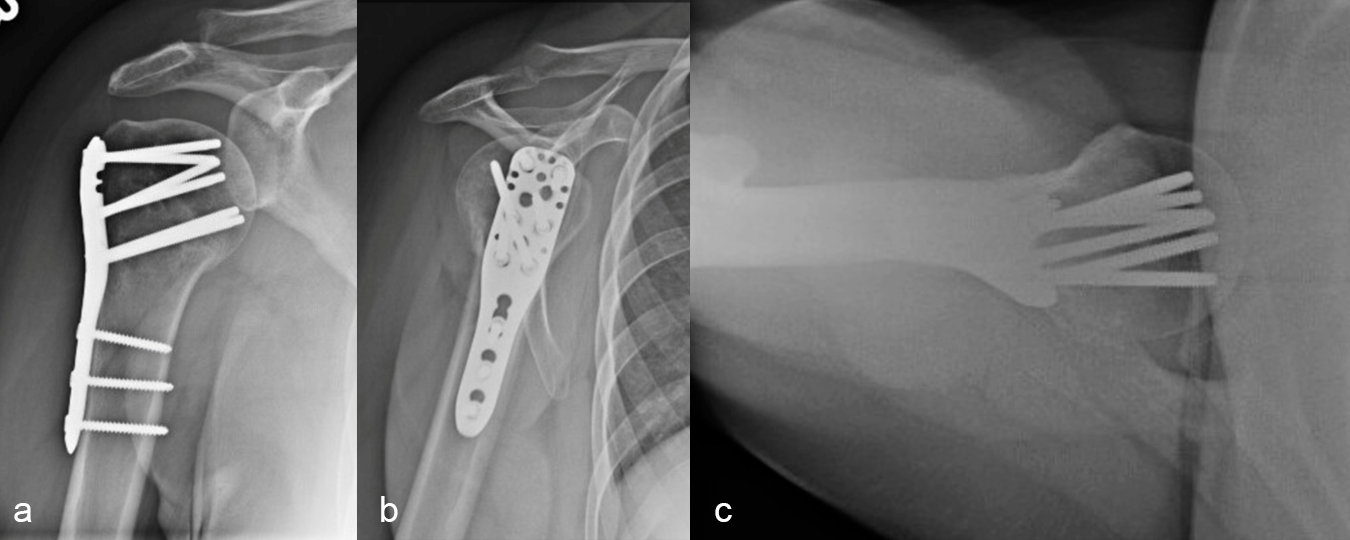

Definitive fixation was performed with a 3-hole VOLT™ Proximal Humerus plate (Fig 4). The plate was placed just beneath the rotator cuff insertion to directly support the greater tuberosity component. The proximal screws angulated toward the superior head to maximize length. The calcar screws were placed in a slightly splayed trajectory. One of the angular stable variable angled screws in the central portion was angulated in a posterior and more central position. This permitted maximal screw spread within the humeral head.

Three months after surgery, the patient had good elevation in the scapular plane to 130 degrees. External rotation was measured at 30 degrees, with more limited internal rotation (to the belt line). X-ray imaging (Fig 5) showed maintenance of fracture alignment and no change in screw position. The axial view (Fig 5c) highlights the subchrondral position of the variable angular screws in the humeral head. The patient was progressing nicely with functional tasks and adding weight in her therapy program.